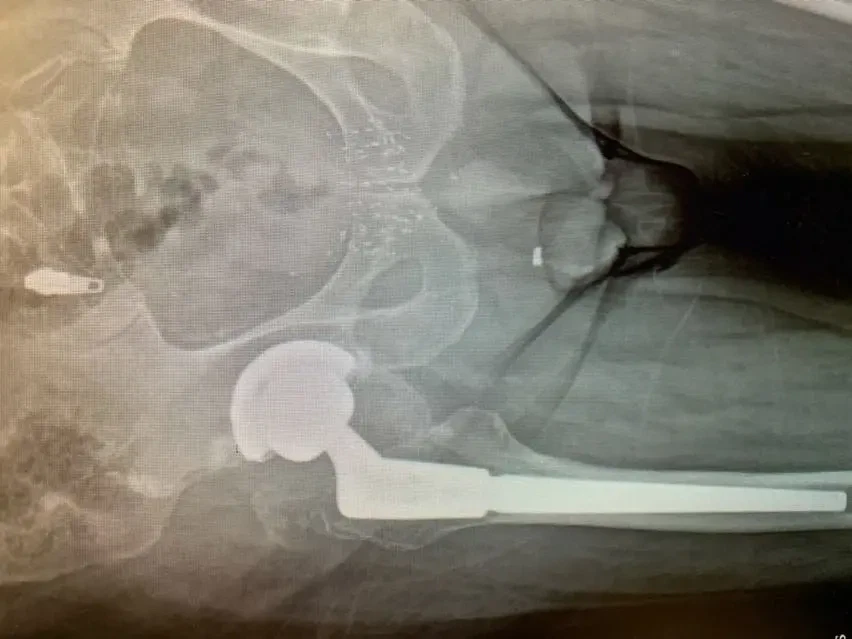

Las radiografías simples revelaron un adelgazamiento y «penciling» del cuello del componente femoral, lo que indicaba una probable corrosión por rozamiento en la muñonera, también conocida como «muñonosis». De hecho, las radiografías indicaban que la unión estaba tan corroída que se había fracturado. Investigaciones posteriores revelaron que el tipo de componente utilizado en la primera operación de sustitución presentaba este fenómeno en mayor proporción que otros, aunque esto no se sabía en aquel momento.